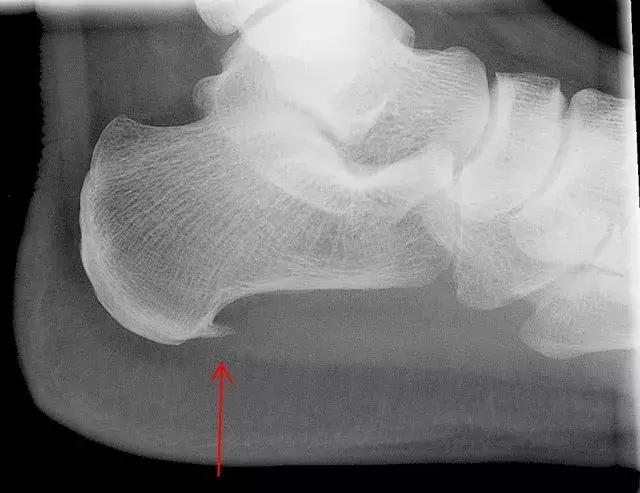

通常不需要影像检查来确诊。 医生可能会建议你拍X光片或做磁共振成像来排除其它可能引起足跟疼痛的原因,例如压力性骨折或神经压迫等原因。

有时X光片显示从脚后跟有向前突出的骨刺。 在过去,人们认为这些是骨刺引起了脚跟疼痛,需要手术切除。 但是后来发现许多有骨刺的人并没有脚后跟疼痛而且手术去除骨刺也没有改善症状。所以,目前认为,骨刺本身并不是引起疼痛的直接原因。有些骨刺可能会引起足底筋膜损伤,产生炎症反应才导致疼痛